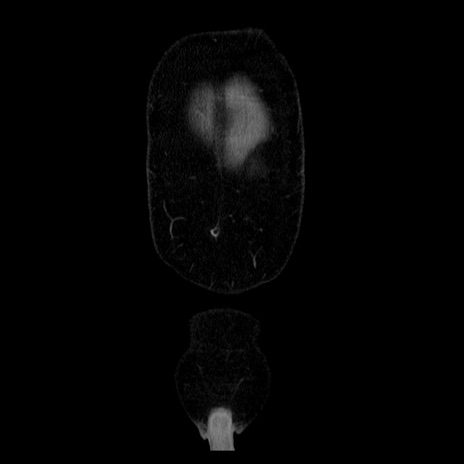

横断像